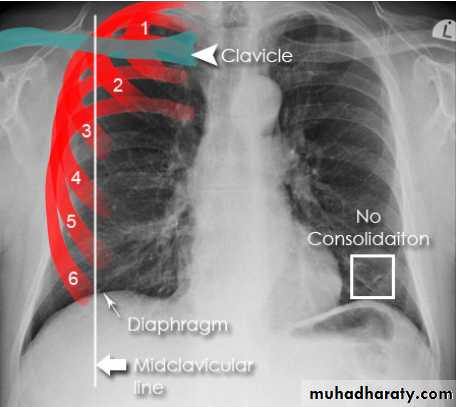

• 1- trace the diaphragm: the upper surface of diaphragm should be clearly visible from CPA to other, except when heart and diaphragm in contact with diaphragm.

On good insp., the dome of rt. Hemidiaphragm at level of ant. End of 6th rib.

The rt. Hemidiaphragm being up to 2.5 cm higher than the left.

8- assess technical quality of the film: correctly exposed routine PA CXR is one in which the ribs and spine behind the heart can be identified but lung not overexposed.straight film is one where the medial ends of clavicles are equidistant from thoracic verteb.